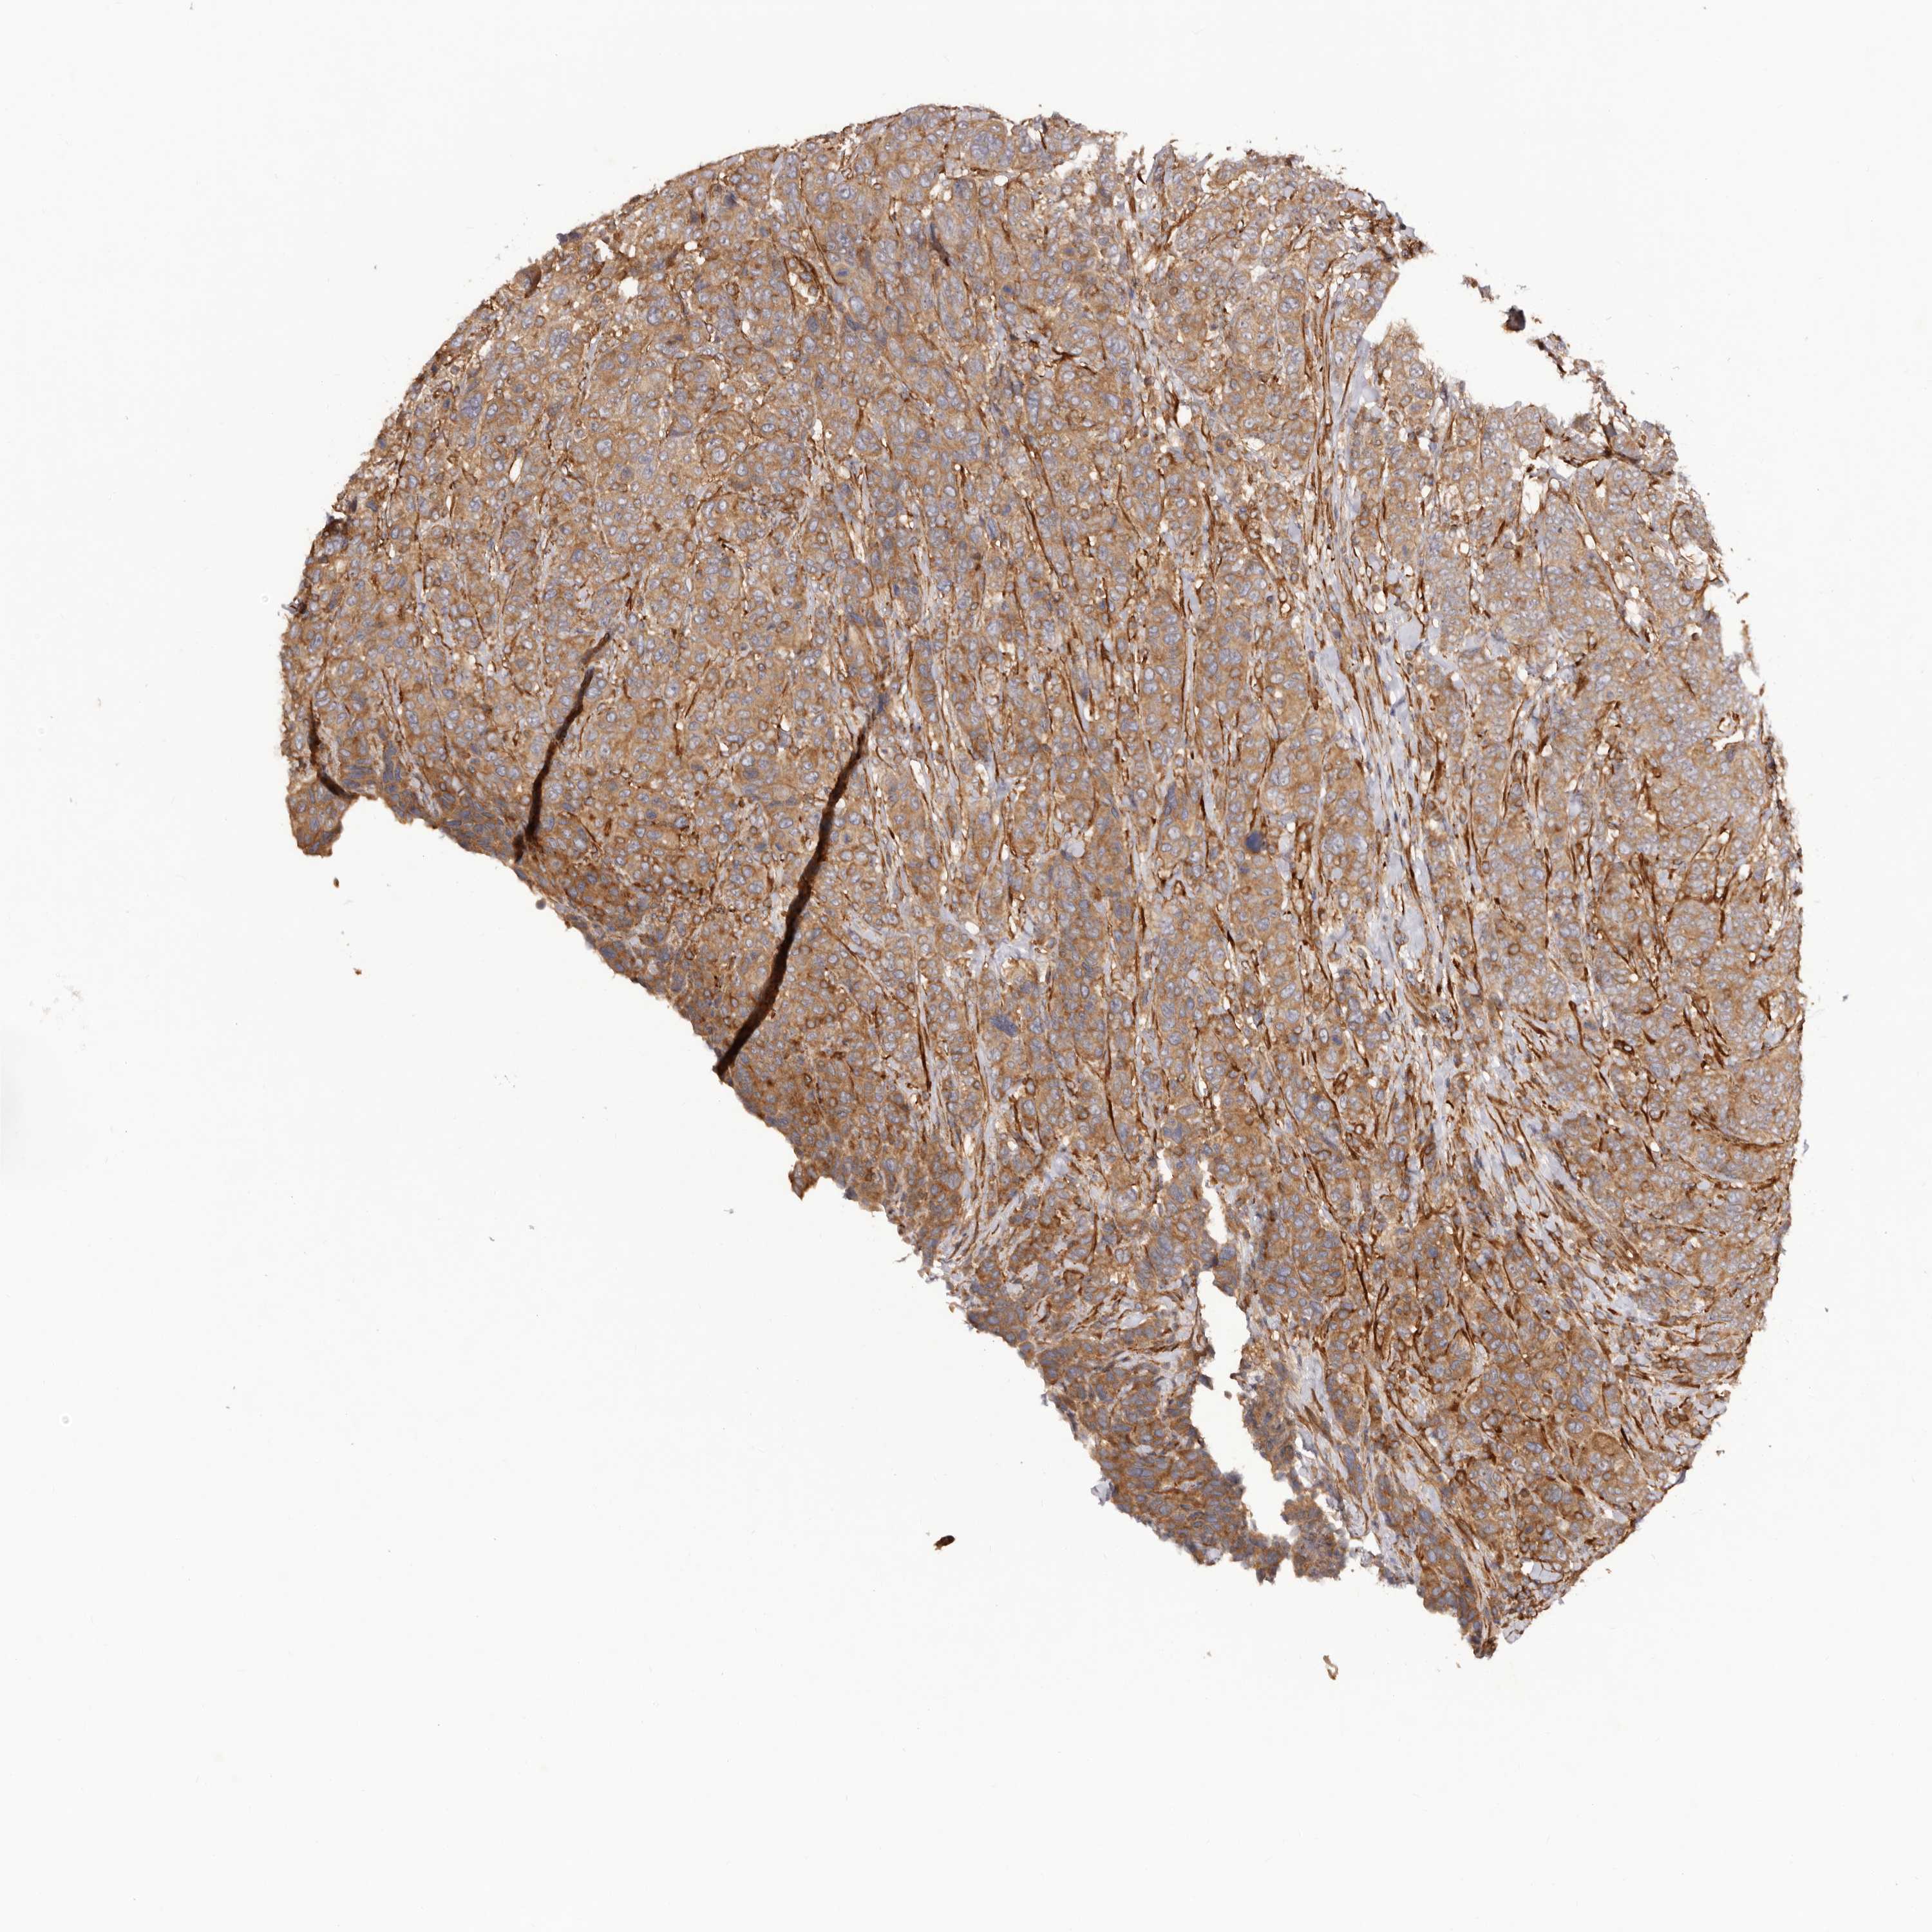

CANCER BREAST CANCER Show tissue menu

BRCA TCGA BRCA VALIDATION PROTEIN EXPRESSION

ANTIBODIES

AND

VALIDATION